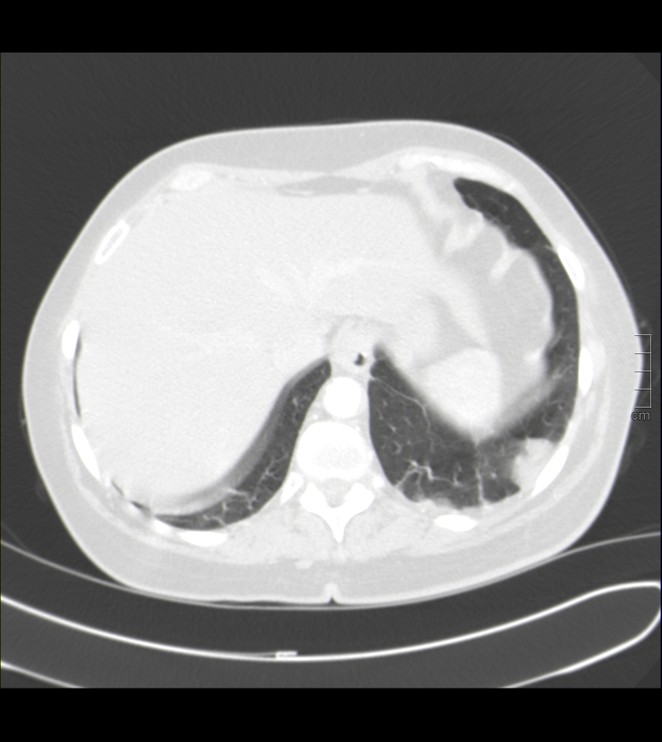

Múltiples defectos de repleción indicativos de tromboembolismo pulmonar, bilateral que afecta a ramas principales de ambas arterias pulmonares y a varias lobares y segmentarias del lóbulos superiores e inferiores.

En cortes inferiores encontramos estos hallazgos: